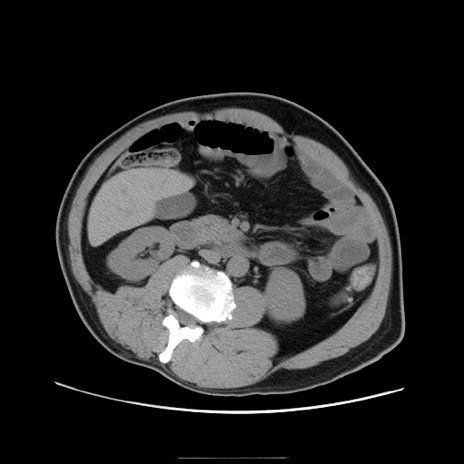

冠状断像

【症例】50歳代男性

【主訴】腹痛

【現病歴】AVMからの被殻出血のため回復期リハ病棟入院中。 本日午後3時頃急に下腹部痛が出現した。

【既往歴】AVM、被殻出血、虫垂炎、高血圧

【身体所見】意識晴明、左半身不全麻痺、会話の理解は良好、36.5°C、腹部:膨隆、全体に板状硬、下腹部正中に圧痛点あり、反跳痛-、筋性防御不明、右下腹部にope scar

【データ】WBC 9400、CRP 0.06